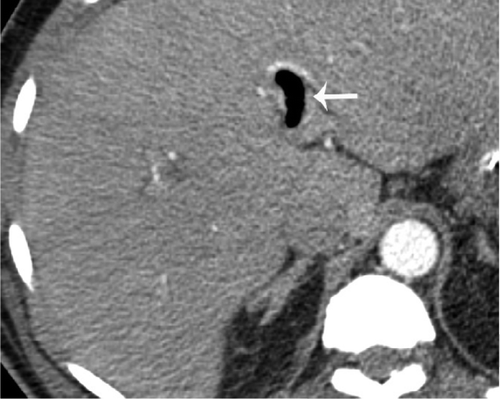

В частности, как пояснил специалист, у некоторых пациентов с COVID-19 внезапно развивался пневматоз - патологическое состояние системы пищеварения, при котором газы проникают в толщу стенки кишечника и образуют там воздушные кисты. Кроме того, у нескольких людей было выявлено необычное желтое обесцвечивание кишечника, еще у трех больных - инфаркт кишечника.

© Radiology